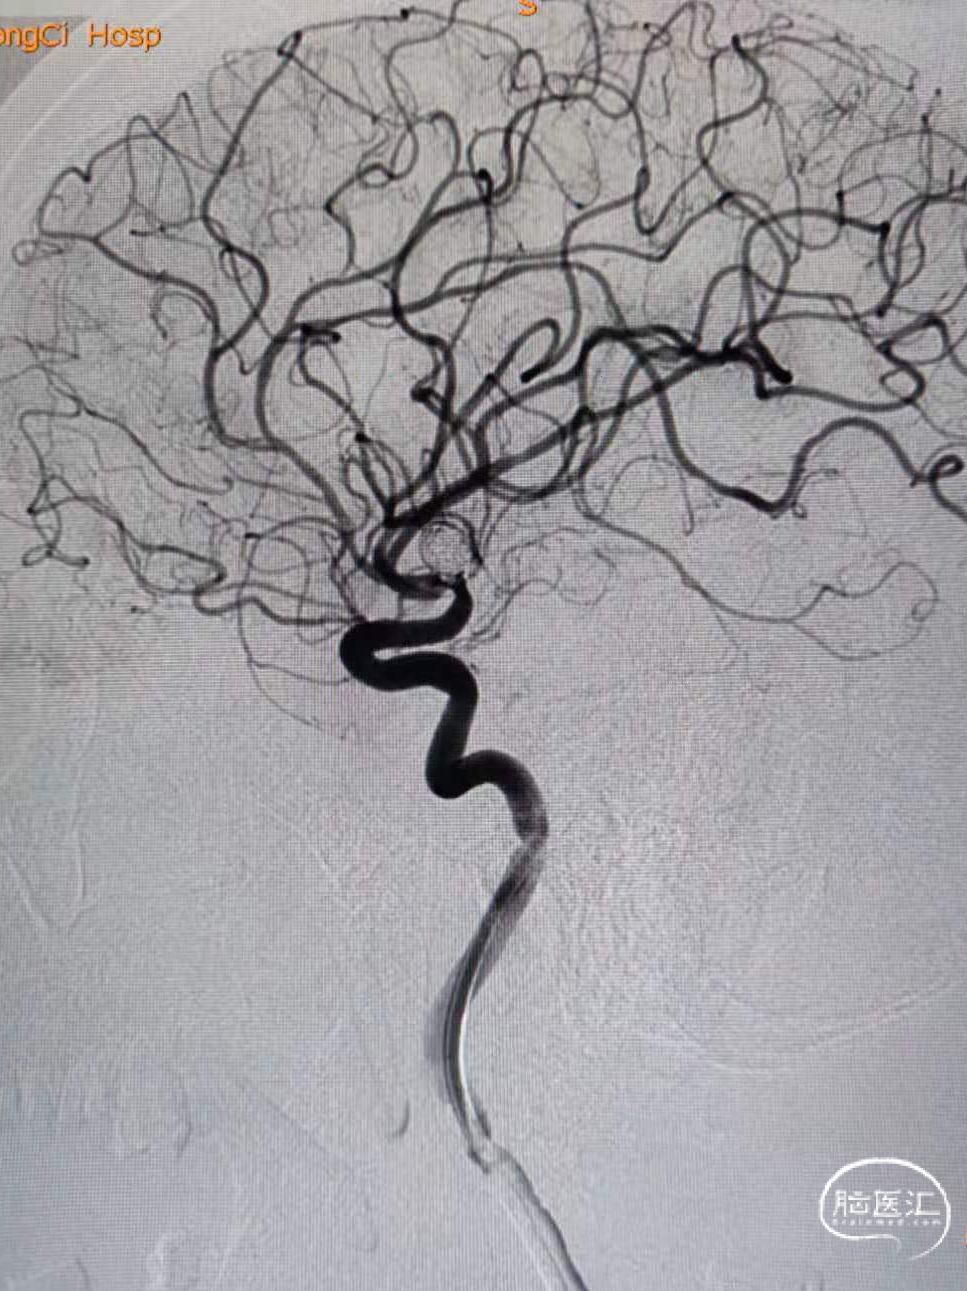

3、随后经送入动脉瘤腔内的微导管连续推送6*20、5*20,4*12、3*8、2*6、2*4弹簧圈。后造影显示动脉瘤栓塞满意,上下支干通畅,显影良好。

1、Atlas支架在小直径血管的表现良好,在本例动脉瘤的到位以及在仅1.0mm的上支干血管内打开顺利,为后续的栓塞治疗提供可靠的保证。